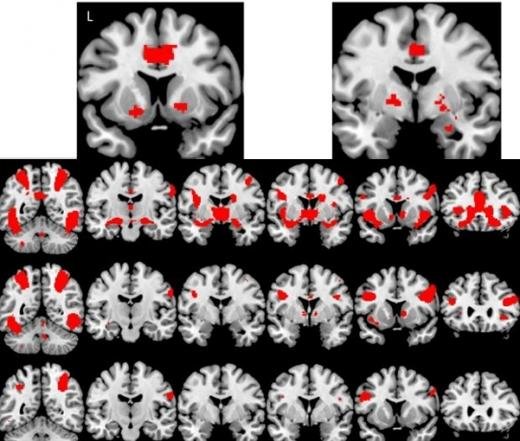

독일 막스플랑크 인간개발연구소에서 진행된 2014년 연구에 따르면, 음란물을 자주 시청하는 남성일수록 우측 선조체(right caudate)와 좌측 측두엽(left temporal lobe) 등에서 회백질의 밀도가 눈에 띄게 감소했다. 또한, 이들의 뇌는 보상 체계의 반응성이 둔화되어, 자극에 대한 민감도가 떨어지고, 더 강한 자극을 찾아나서게 되는 경향을 보였다. 이는 중독성 물질(예: 마약, 알코올)과 유사한 패턴이다.